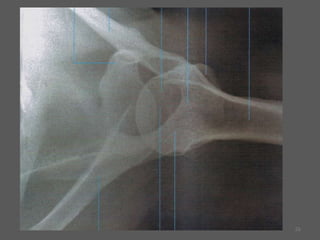

Incidência Ombro lateral em Y escapular – Posição Oblíqua Anterior (túnel supra espinhoso)36

37

38